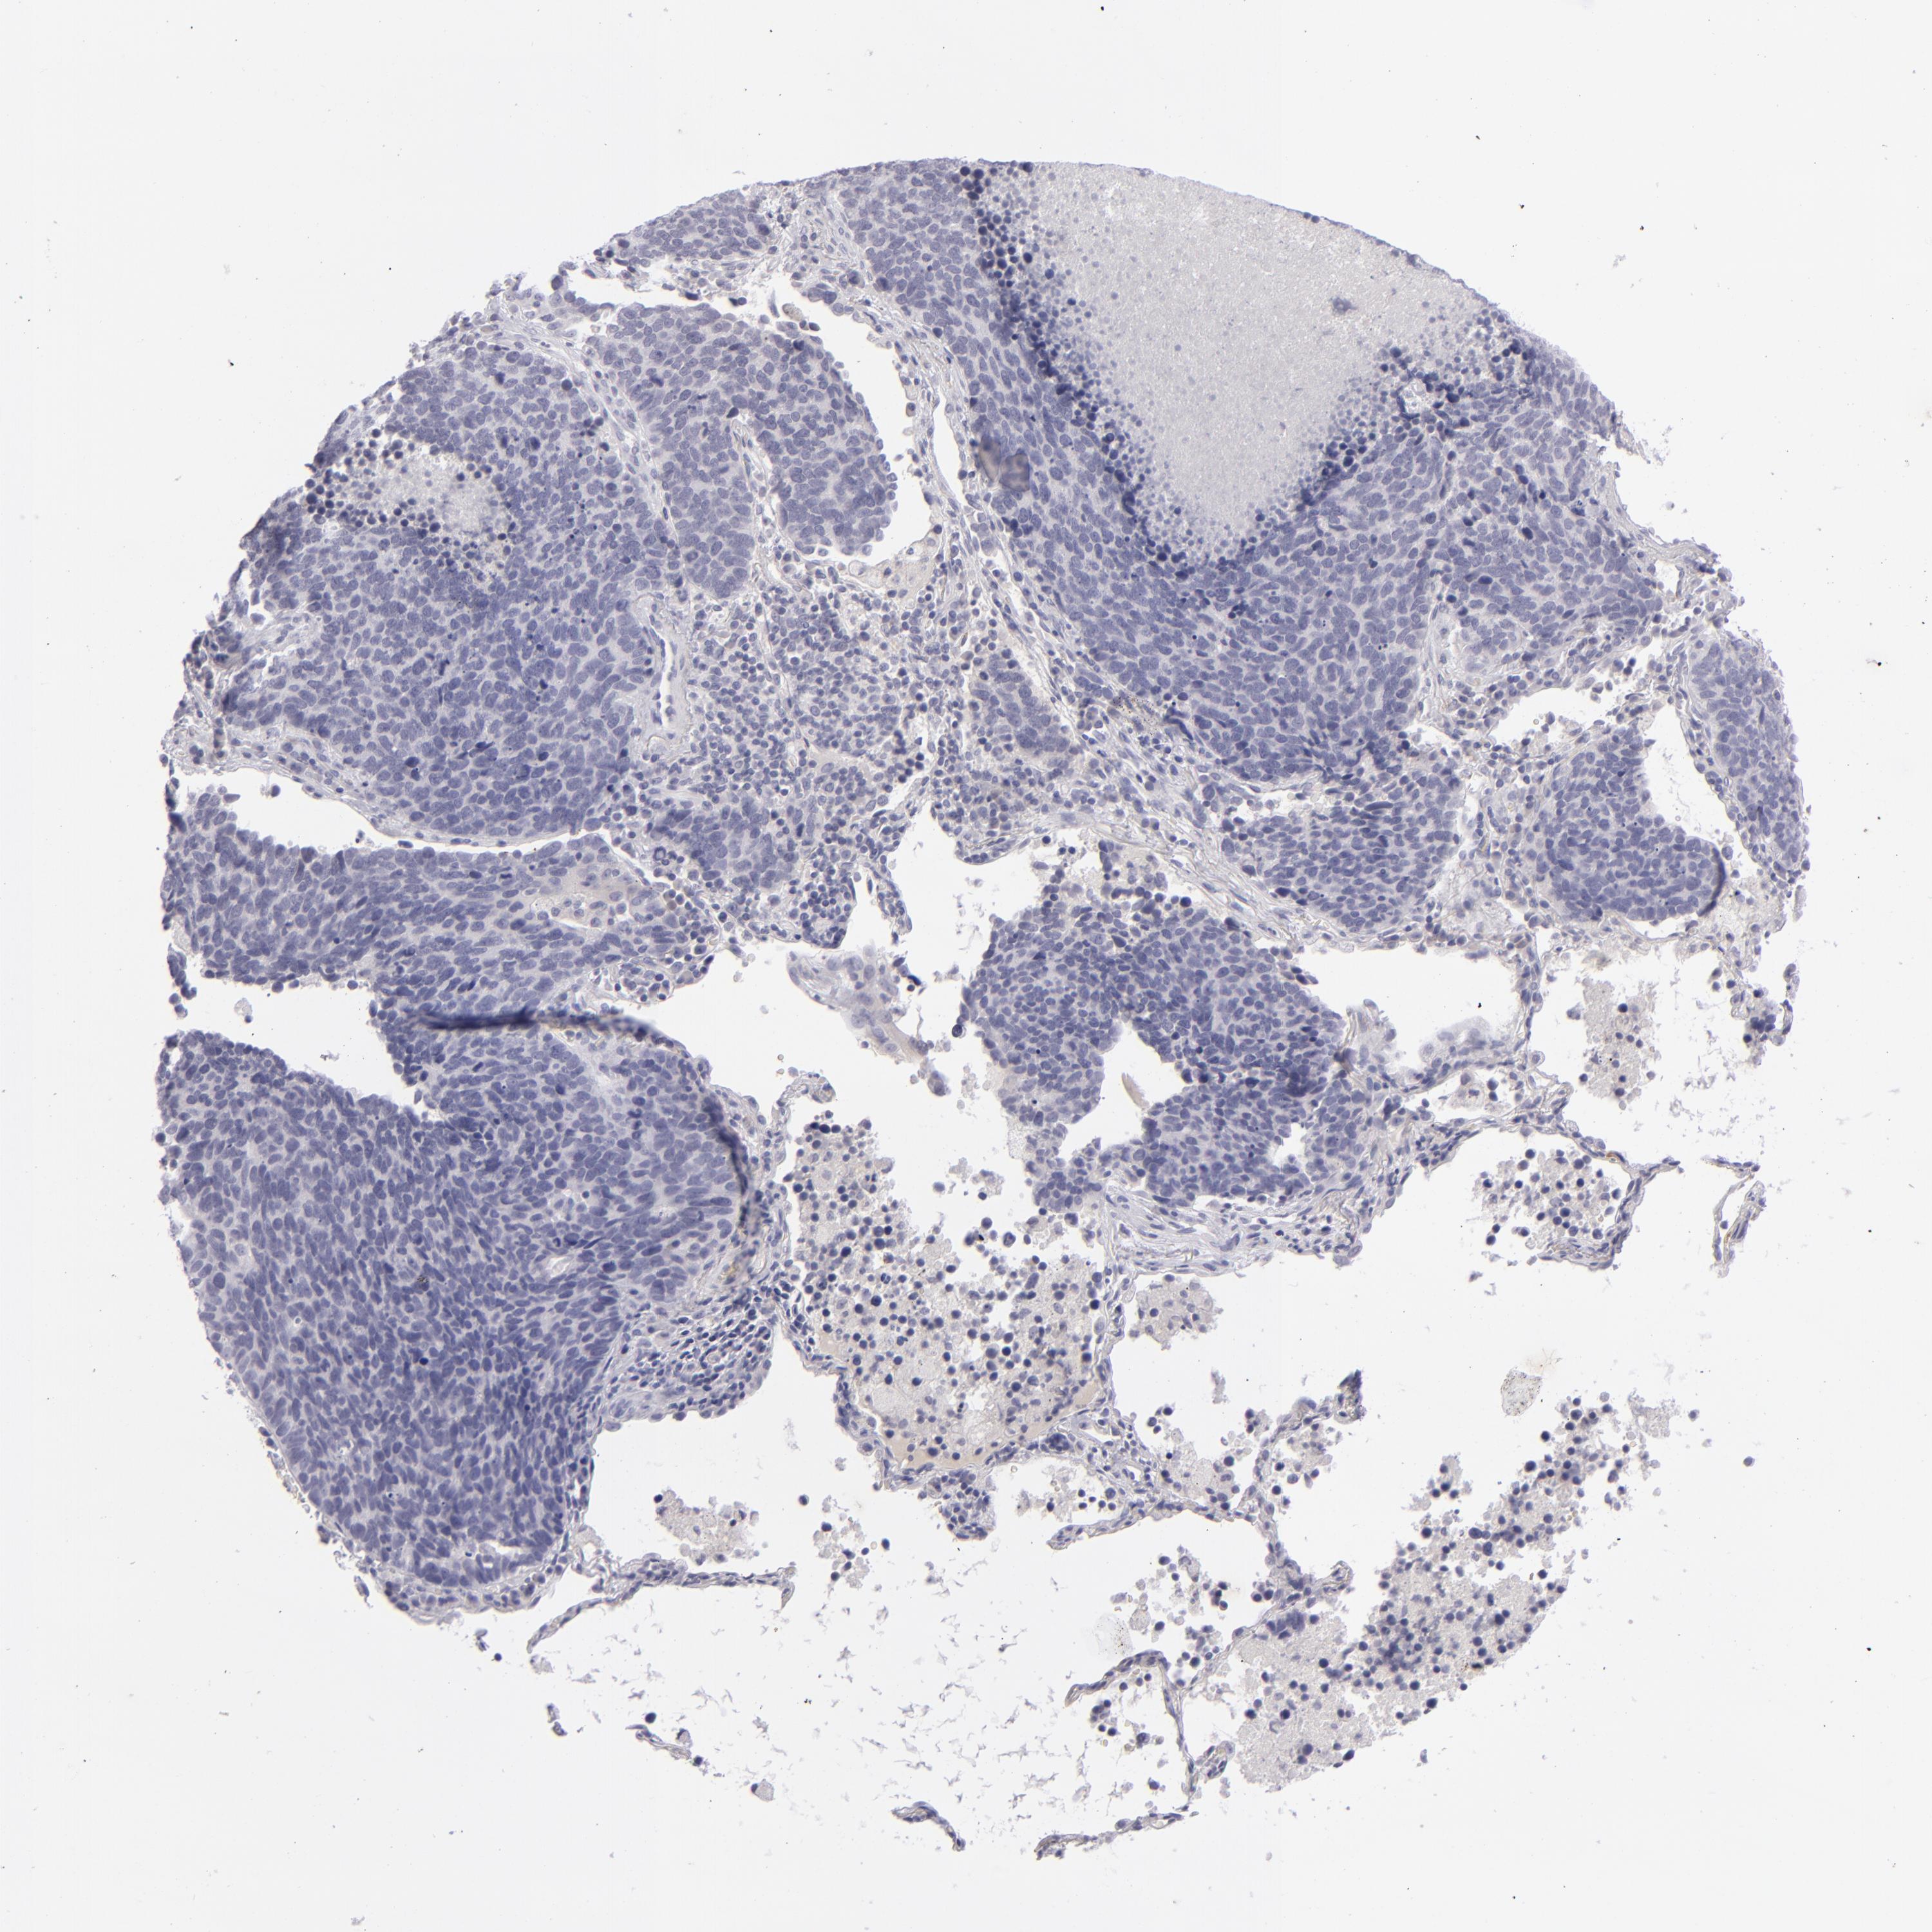

ITGB4 is not prognostic in Lung Adenocarcinoma (validation)

ITGB4 is not prognostic in Lung Squamous Cell Carcinoma (TCGA)